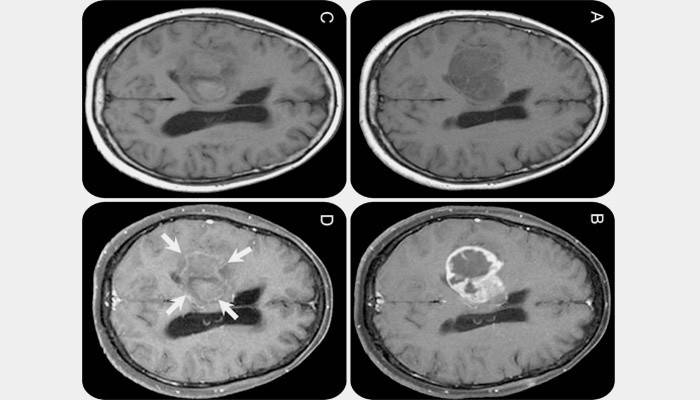

Gdy guz rośnie szybko, nie ma wyraźnych granic, przenika sąsiednie tkanki, jest złośliwy. Istnieje martwica tkanek, krwawienie, często nieoperacyjny rak. Pacjent może umrzeć za kilka miesięcy. Większość pierwotnych nowotworów złośliwych - glejaki - może mieć różny stopień rozwoju. Najszybciej rozwijającym się i najniebezpieczniejszym nowotworem jest glejak ostatnich 4 etapów rozwoju. Więc wygląda na zdjęciu.